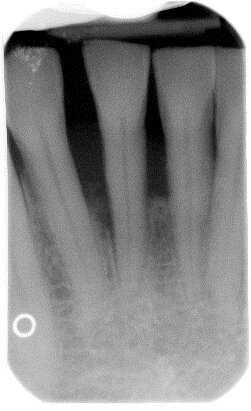

Il Paziente è stato intercettato in visita con diagnosi di parodontite cronica generalizzata da moderata a severa a seconda dei siti. È stata eseguita la terapia non chirurgica in regime di Full mouth disinfection in unica seduta seguita da controlli settimanali fino al raggiungimento della guarigione a 2 mesi dalla strumentazione. In tale fase sulla base della valutazione dei siti con PD>5 mm e dell’anatomia dei difetti infra-ossei o sovra ossei presenti viene normalmente discussa con il paziente la fase di chirurgia correttiva, se necessaria. Nel Paziente in questo caso residuava a livello di 41 un difetto infra-osseo (Figg. 6a-6c).

Fig. 6c - Radiografia iniziale.